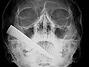

Eles foram vitimas de quedas, acidentes, crimes, ataques de animais e, contra todas as probabilidades, sobreviveram para contar sua historia